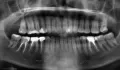

У меня дней 5 ноют зубы с правой стороны так, что не понять какой именно. Больше вверху. Обратилась к врачу - долго искали дырку (стучали, воду лили, воздухом дули), наконец нашли между зубов 5 зуб внизу справа. Удалили нерв, запломбировали. Сказали, что просто отдавало вверх, но когда прошёл наркоз боли возобновились с новой силой! Болит вверху...особенно больно, когда пьёшь тёплый чай или заходишь с улицы. Причём болит от такого тепла не сразу, а минут через 5-10 пошла через день опять, дырок больше не нашли, сделала рентген (причём и вверху и внизу), ничего не увидели...болит! назначили антибиотик...возможно ли просмотреть мой снимок?

На нижней челюсти на седьмом зубе пломба стоит практически на пульпе, из-за чего вполне может быть реакция на холод или тепло. Также в 6 зубе каналы пролечены не совсем хорошо, верхушки не проглядываются (плохое качество снимка).

Для качественной диагностики необходим визуальный осмотр, так как снимок не всегда дает исчерпывающую информацию.